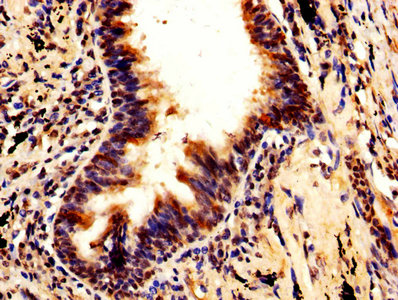

IHC image of CSB-PA896483LA01HU diluted at 1:600 and staining in paraffin-embedded human lung cancer performed on a Leica BondTM system. After dewaxing and hydration, antigen retrieval was mediated by high pressure in a citrate buffer (pH 6.0). Section was blocked with 10% normal goat serum 30min at RT. Then primary antibody (1% BSA) was incubated at 4°C overnight. The primary is detected by a biotinylated secondary antibody and visualized using an HRP conjugated SP system.